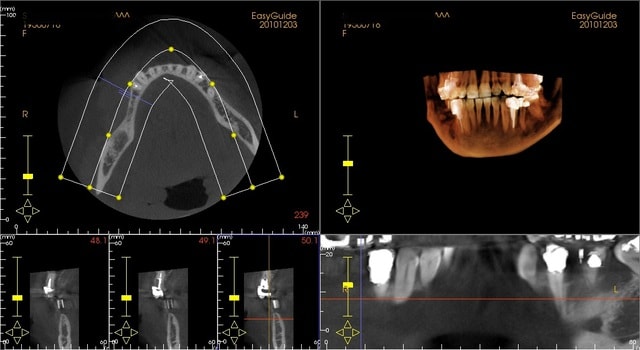

il s'agit d'une patiente que je dois implanter en 44 45 46, avec une crete fine; ça doit passer pour 45 46 mais en 44 ça me parait un peu limite qd même.

c'est pas très lisible ton truc sur nonol...

tu peux mettre que les coupes (seules) légendées/dent ainsi que tes mesures par écrit...çà simplifierait les choses